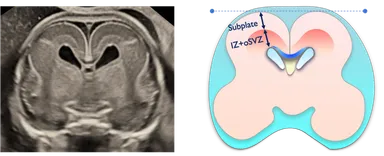

夫 律子院長が発表した研究は、胎児の脳における「サブプレート」と呼ばれる脳層に着目したものです。サブプレートは胎児期の一定の時期にしか観察されることがない特殊な脳層で、ヒトの大脳皮質形成初期においてニューロンの移動や神経回路の形成に重要な役割を果たし、神経発達の鍵を握る構造として注目されています。このサブプレートに着目して実際の胎児での観察実績をもつのは現在のところ世界でもクリフム出生前診断クリニックだけです。※当院調べ

方法:高精度3D経膣脳神経超音波による脳の詳細計測

クリフム出生前診断クリニックでは、胎児ドック全例において定量的・定性的な胎児脳評価を行う「胎児脳ドック」を標準実装しています。一般的な妊婦健診では実現困難な高精度胎児脳評価を通じて、人間にとって最も重要な器官である脳の発育を胎児期から詳細に診断しています。これまでは「生まれて育っていく過程でしかわからない」とされていた神経発達を胎児期より詳細に観察し、胎児脳研究で世界をリードする存在です。

胎児脳の診断はここまで精密な画像で行わなければならないと夫医師は話す